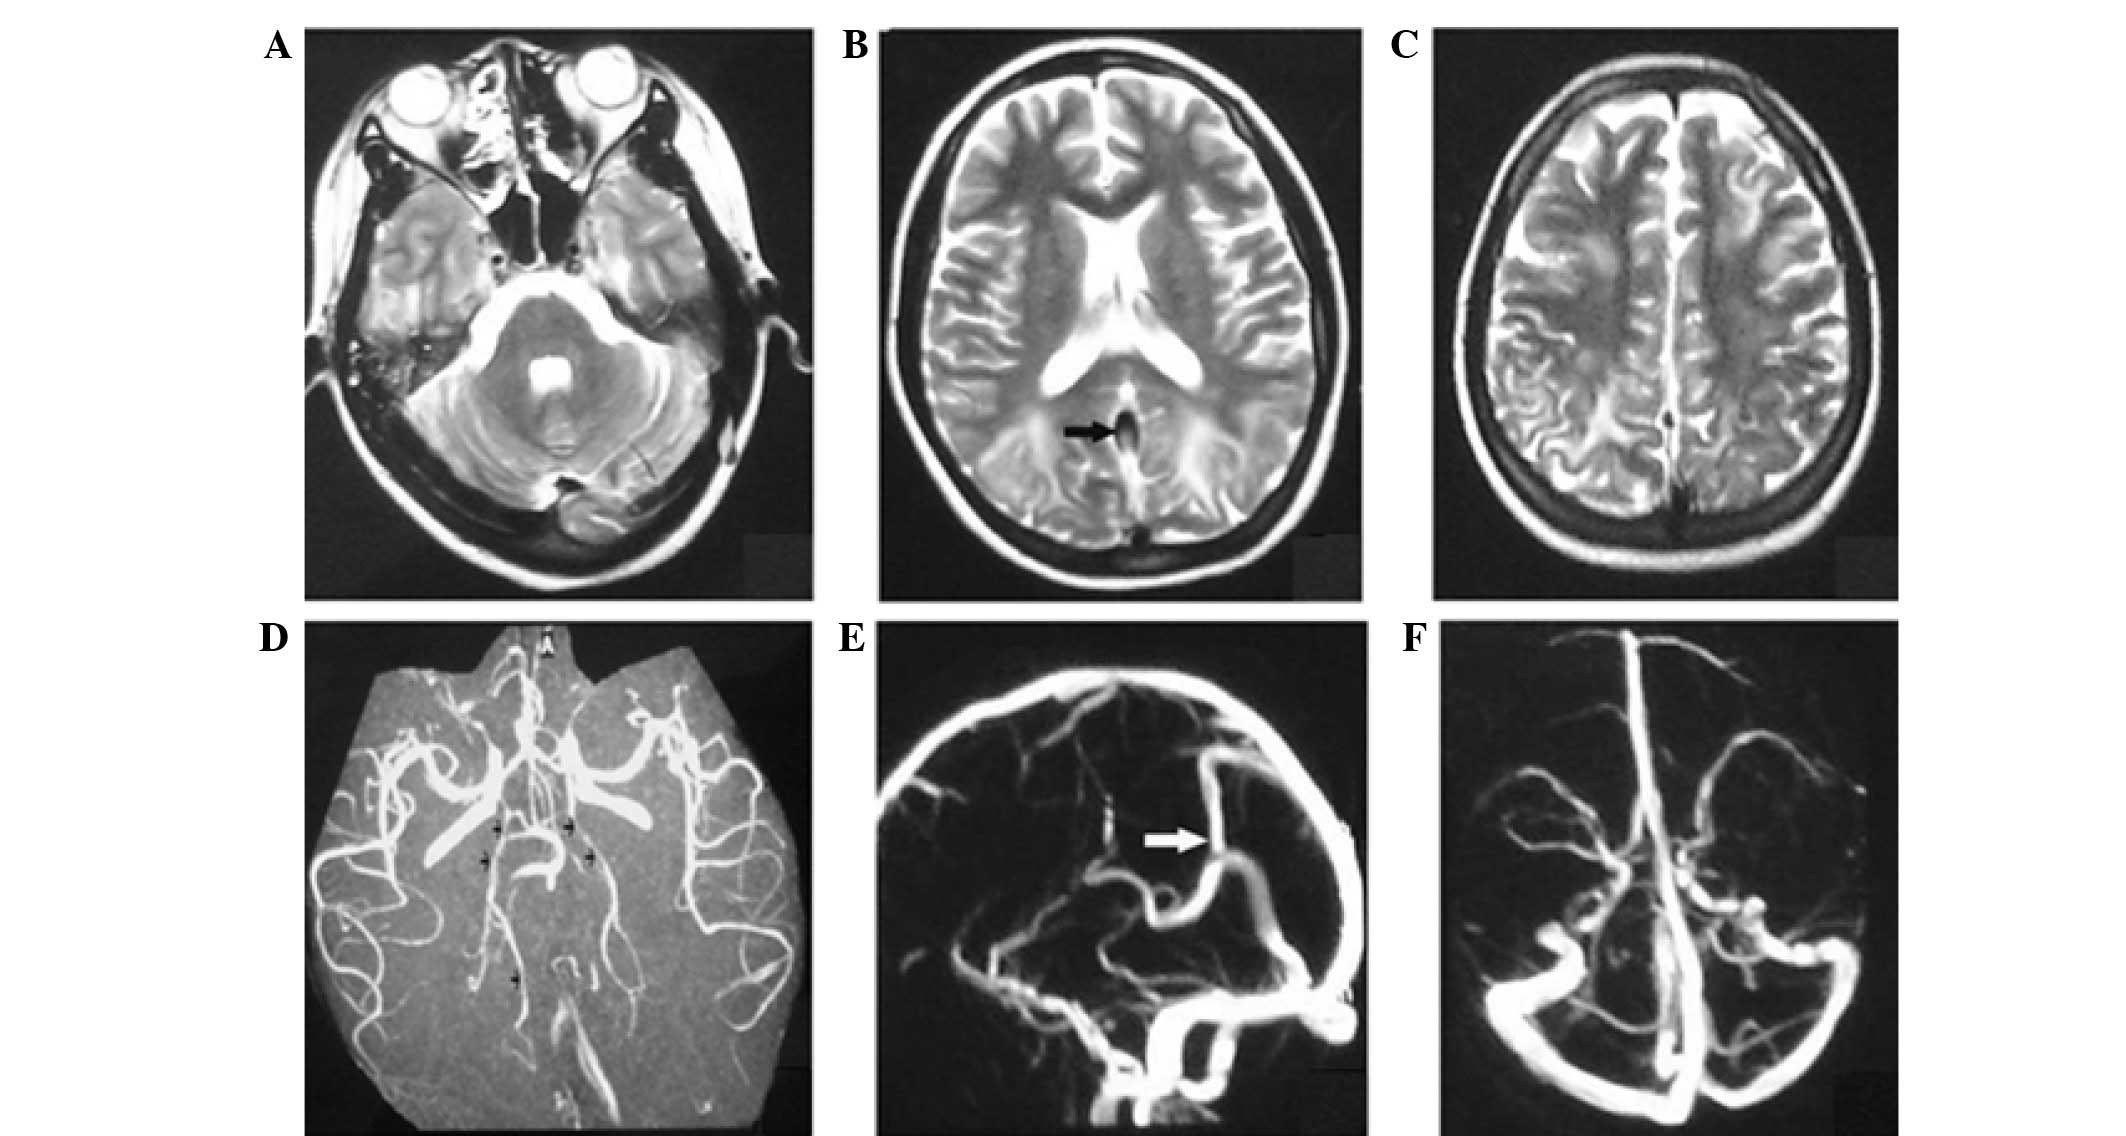

A neurological examination indicated a somnolent state without any focal neurological signs. Laboratory blood tests revealed leukocytosis (white blood cell count, 16,000 cells/mm3; normal range, 3,500–9,500 cells/mm3) with left-shifting. A head magnetic resonance imaging (MRI) scan was performed, which indicated multiple foci of high signal intensity on T2-weighted images and fluid-attenuated inversion recovery (FLAIR) sequences in the cortical and subcortical white matter bilaterally, predominantly in the occipital, frontal and parietal lobes and cerebellum (Fig. 1). In addition, diffuse weighted imaging (DWI) revealed no evident abnormalities (Fig. 1). Following admission, the results of cardiovascular, respiratory, abdominal, neurological and ophthalmologic examinations were normal. Laboratory tests were also normal, including urinalysis, serum electrolytes, liver function, glucose and lactic acid levels, coagulation profiles, serological assessment (including the venereal disease research laboratory test, and tests for thyroid hormones) and an autoimmune profile (which involved assessments for antinuclear antibodies, double strand DNA, antineutrophil cytoplasmic antibodies and antiphospholipid antibodies). A lumbar puncture was also performed, and the cerebrospinal fluid opening pressure, protein, glucose, immunoglobulin and the number of cells were found to be normal.